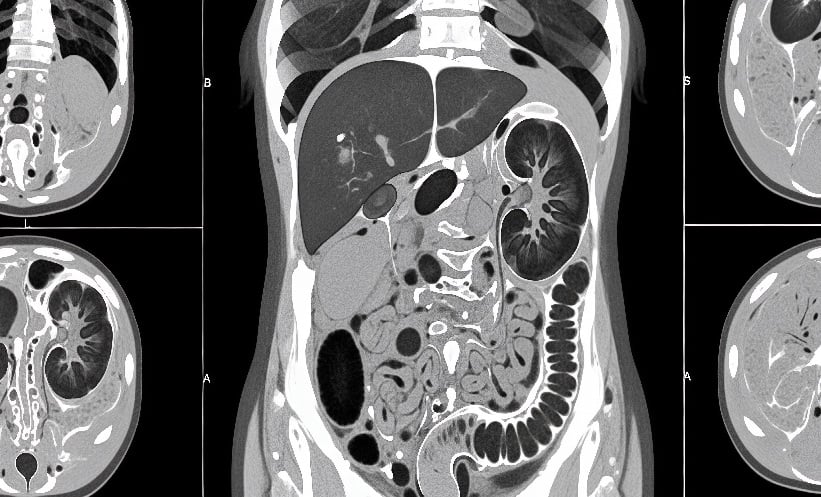

Rising CT Scans in Elderly Raise Radiation Questions – EMJ

Gradual Rise in CT Scans Among Older Adults

AT A SINGLE quaternary-care academic hospital, the proportion of computerised tomography (CT) scans performed on patients aged 60–90 increased from 50.4% in 2014 to 58.3% in 2024. This trend raises…